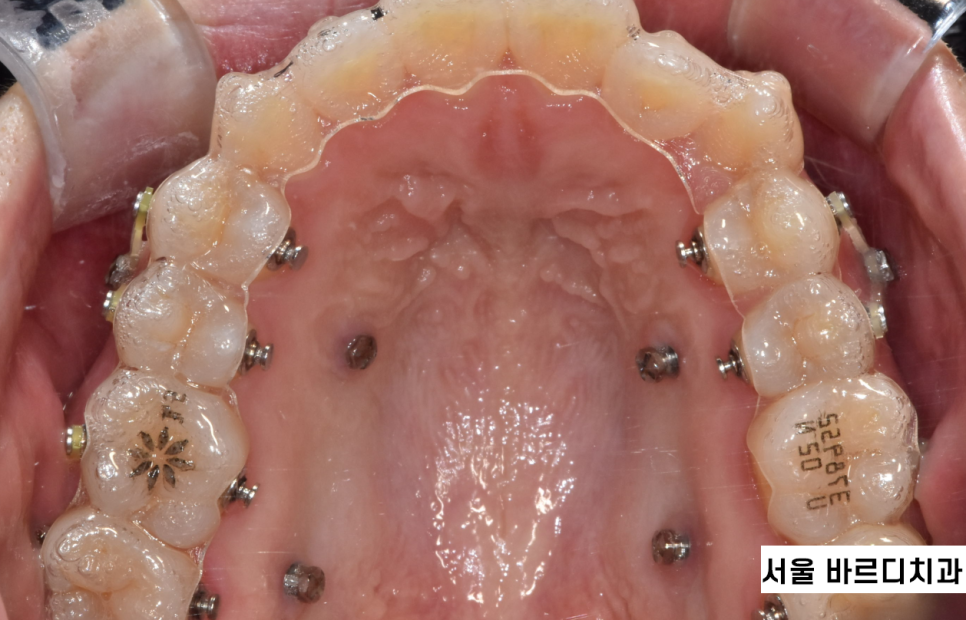

장치제작은 구강 스캐너를 사용하여 디지털 방식으로!

투명교정 역시 전통 교정 방식이 아닌

최신 기술로 등장한 것이잖아요~

인비절라인, 시스루테크

2가지 투명교정 모두 디지털 방식으로 치아를 스캔한답니다.

찰칵 찰칵 사진찍듯이

구강구조를 파악하는거죠~~

- 투명교정 장치 제작

치아 이동 계획에 따라 개인 맞춤형 투명교정 장치가 제작됩니다.

투명교정 장치는 일반적으로 1~2주 정도의 시간이 소요되며,

각 장치는 단계별로 조금씩 다른 치아 이동을 유도하도록 설계됩니다.